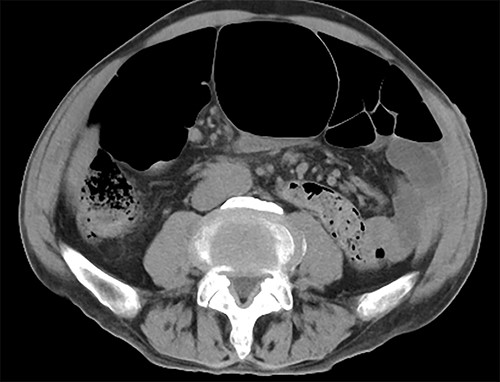

The transanal ileus tube was removed after the introduction of anesthesia. A 12-mm port was inserted at the umbilical site and insufflated for intra-abdominal observation. An additional 5-mm port was placed in the right midline for observation (Fig. 3).

Surgical findings. Twelve millimeter port was inserted at the umbilical site and an additional 5-mm port was placed in the right midline for observation.